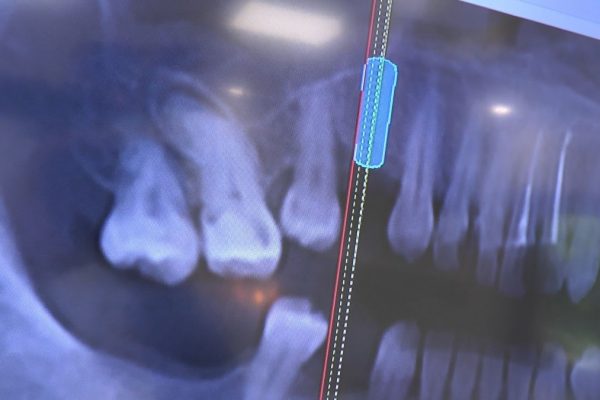

W ostatni weekend czerwca 2018 roku kursanci II Sezonu Preludium Implantologii odbyli piątą, finałową sesję, która w całości podporządkowana była praktyce. W ciągu dwóch dni zabiegowych Lekarze uczestniczący w szkoleniu przeprowadzili szereg zabiegów pod kierunkiem dr n.med. Violetty Szycik. Wszczepili 17 implantów oraz przeprowadzili ekstrakcje i zabiegi regeneracyjne kości. Zabiegi były wykonywane także w sedacji dożylnej z udziałem specjalisty anestezjologii i intensywnej terapii dr Jolanty Grzybowskiej. Preludium implantologii to nowy program edukacyjny dla adeptów implantologii stomatologicznej, którego celem jest wprowadzenie do implantologii poprzez pozyskanie wiedzy w szerokim zakresie i uwzględnieniem szczegółów mających decydujące znaczenie dla powodzenia leczenia implantologicznego. Ale tak jak wszystkie szkolenia w Instytucie Vivadental, w tym wiodące Practiculum Implantologii, zorientowane jest na praktyce i samodzielnym wykonywaniu zabiegów pod kierunkiem Mentora. To najlepsza edukacja w medycynie zabiegowej, a zarazem najlepszy start do implantologii.